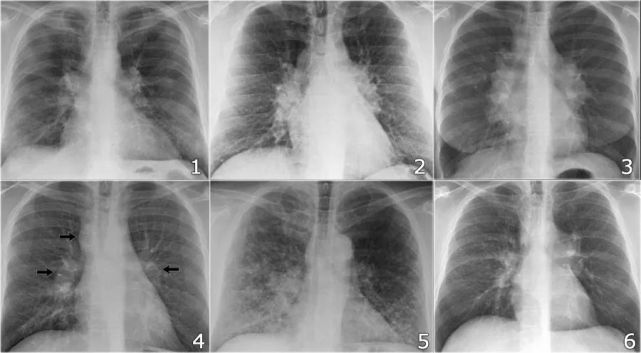

胸水胸片典型图片

胸水胸片典型图片,

当胸腔积液量达到300mi时,外侧肋膈角变钝,在正位胸片,上可见.